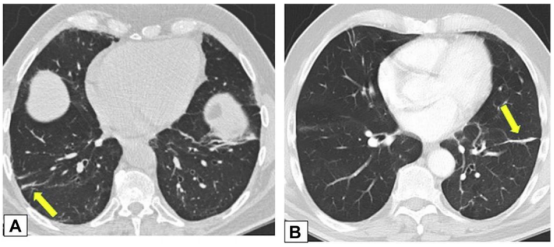

实变是OP病例中最常见的发现,发生于近75%的病例中,病变通常在双基底、支气管血管周围和/或外周。图1A为一名女性患者,右肺上叶周围实变,其曾因乳腺癌接受过放射治疗,并经活检证实为OP。图1B患者左肺下叶和舌叶周围实变,活检证实为继发于淋巴瘤化疗的OP。

图源:Chest, 2022, 162(1):156-178.

在活检证实的OP患者中,中肺(图2A)和下肺(图2B)的增强CT扫描图像显示双侧多灶性支气管血管周围实变灶。

图2 支气管血管周围实变

图源:Chest, 2022, 162(1):156-178.图3A为71岁男性,2011年7月因劳力性呼吸困难就诊,胸片显示右肺上叶实变。图3B为2012年6月再次检查显示右肺上叶异常已消失,左肺出现广泛实变。图3C为2013年6月,左肺病变消失,但右肺下叶出现新的实变。这些发现是典型的OP游走性表现。图源:Chest, 2022, 162(1):156-178.图3所示患者胸部CT可见磨玻璃影伴小叶间隔增厚和铺路石征的游走灶(图4)。由此可见,OP的实变可以发生在肺的任何部位,边界清晰或模糊,呈游走性特点。图源:Chest, 2022, 162(1):156-178.OP的实变可以呈局灶性、多发性和弥漫性,也可以表现为结节或肿块。图5所示患者为70岁女性,COVID-19确诊9个月后出现持续气促,CT平扫图像显示支气管血管周围多灶性肿块样实变。在类固醇治疗后症状显著改善,实变消退,推测诊断为OP。图源:Chest, 2022, 162(1):156-178.实变常伴支气管充气征,可伴散在的磨玻璃样低密度或小实质结节。以主要的或完全的磨玻璃低密度为表现者较少见。图6A所示为一名有甲状腺乳头状癌病史的47岁男性患者碘131治疗4个月后的CT平扫图像,可见右肺上叶支气管血管周围磨玻璃影。PET/CT扫描显示磨玻璃影代谢增高(图6B)。CT平扫图像显示左肺上叶新出现的磨玻璃影(图6C)。支气管活检结果与OP相符。图源:Chest, 2022, 162(1):156-178.图7为一名71岁男性患者因使用胺碘酮导致SOP的CT平扫图像,可见左肺广泛磨玻璃影,小叶间隔增厚(铺路石征)。磨玻璃低密度影合并小叶间隔增厚可表现为铺路征。